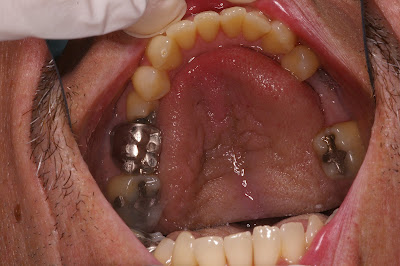

Here are the Invisalign patient's before photos.

When I get back to the office next week I plan to set up blog that will follow one of my Invisalign patients. I hope to track his progress with pictures at each visit. Changing someones smile and improving their appearance is one of the more enjoyable things we do at the office. We are a small cosmetic and general dental office located in Saint Petersburg, FL.